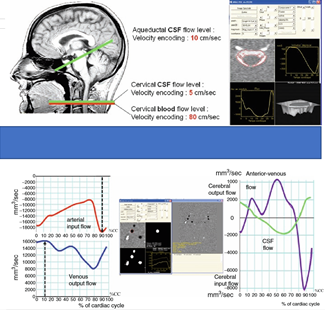

磁共振检查测量脑脊液流动速度,就如同检查MRA一样,磁共振利用垂直于磁共振扫描面的液体流动,在磁共振不同时像信号的不同,经过一个心跳周期,液体流动的变化可以通过影像计算其流速,一个心跳周期32幅影像。如下图,通过流速敏感软件测量后,我们就了解局部脑脊液流速。把这些局部流速数据模拟成每个心跳周期的液体流动,我们就可以动态的看到脑脊液大概的动力学运动情况,来判断动力学存在不存在问题了。

这些数据经过处理后变成各种静态的曲线数据和动态的脑脊液流动模拟图像,就可以帮助我们无创地评判脑脊液在脑组织中是否存在问题,是什么样的问题,是否可以手术方法解决;解决后,如何评判治疗效果,长期跟踪病人情况。不需要我们做腰穿测压或引流,或腰穿脑压监测或开颅脑压监测。这是一个很好的工具。专业人士也好,病人也好,都需要知道并合理利用。